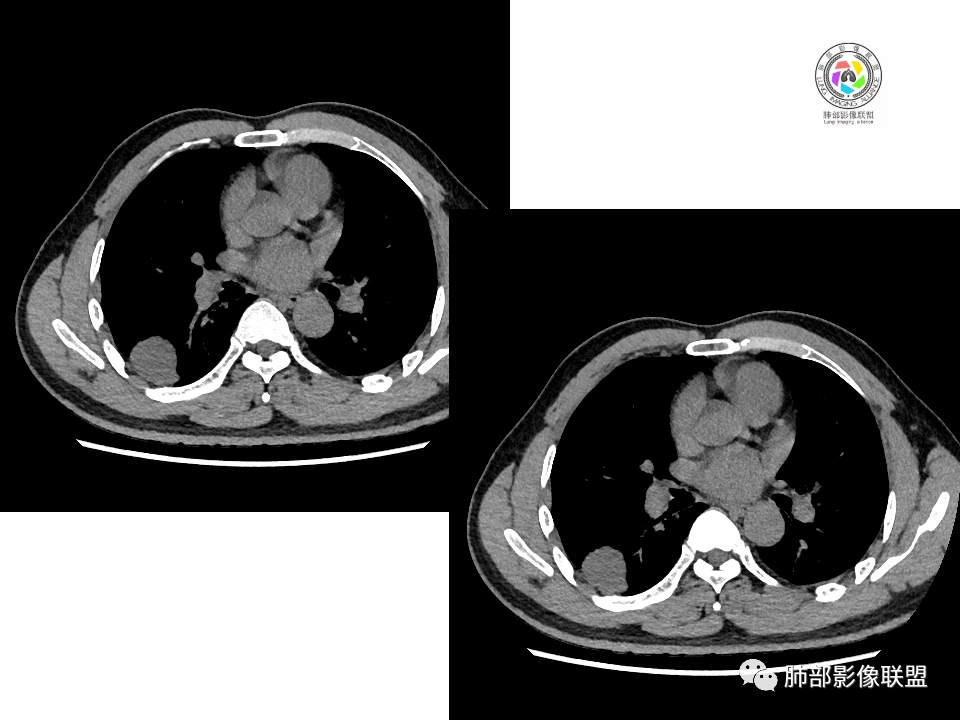

中年男性,体检发现占位。右肺下叶背段胸膜下肿块,周围晕征,有小分叶,与支气管、肺内血管关系不清,形似山丘,重建可见肿块呈D字形凸向肺部。似跨斜裂,似有小凸起与肋下缘相连,增强似有轻微均匀强化。右肺下叶外基底段小结节,位于血管周围,部分边缘平直,轻微均匀强化。考虑二元:一、右下叶背段肿块为肺外病变,神经鞘瘤?SFT?鉴别小细胞癌、隐球菌病;二、右下叶外基底段结节考虑为良性结节、炎性肉芽肿?

大小两个结节,形态类似,强化一致,都是乏血供病变,也无明显坏死,不符合炎性肉芽肿强化特点了,大结节膨隆明显,有局部突出,有长期吸烟史,所以考虑神经内分泌肿瘤可能(小细胞>不典型类癌),另外不典型错构瘤需要鉴别。最终还是需要穿刺病理确定。

南边:这两个一元论的病灶考虑:

①炎性:隐球菌;

②恶性:间叶来源肿瘤,间叶来源的两个病灶的罕见;癌一般还是与支气管关系密切,有如果考虑癌,自然是小细胞癌(山丘征);但是因为没有看到支气管具体情况,不太踏实。

显然本例焦点在于背段那个边缘光整的块影!

1.边缘光整干净,大病灶缺乏坏死等,不符合鳞癌影像学特征。尽管有吸烟史,还是偏年轻。

2.边缘光整,会是小细胞癌或是大细胞癌吗?小细胞癌的肺门纵隔淋巴结增大往往十分夸张,该患者不符合。

注意,基底段支气管血管束旁的小结节影,即便是淋巴结,也与背段病灶引流途径不符。

4.良性占位绕不过去,如发生于该部位的孤立性纤维瘤等……

病灶不均匀强化可以将含液支气管囊肿排除在外。

5.慢性感染灶。缺乏临床表现,强化不显著会想到继发性肺结核,背段病灶过于光整均匀,周边过于干净使人狐疑,且“成掎角之势”的中叶病灶结核灶特点也着实不多。

有老师分析,多发病灶有磨玻璃晕,可以符合隐球菌感染,确实如此。但背段边缘如此锐利的块影还是更容易让人联想到新生物。